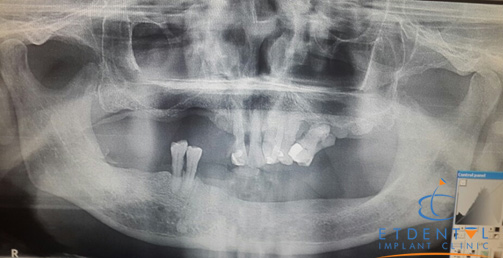

Phim chụp toàn cảnh trước điều trị